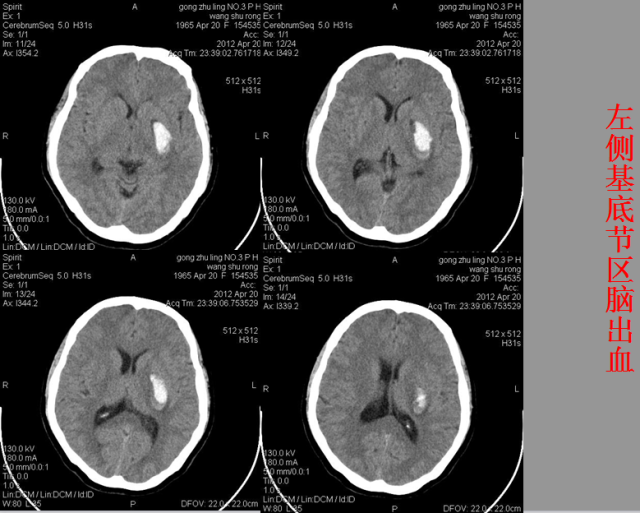

急性颅脑损伤篇

急胸症篇